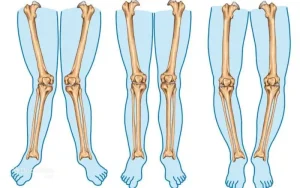

عوارض انحراف زانو

انحراف زانو شاید در نگاه اول فقط یک تفاوت ظاهری به نظر برسد؛ پاهایی که کمی پرانتزی یا ضربدری هستند و خیلیها با آن زندگی میکنند. اما واقعیت این است که انحراف زانو، اگر نادیده گرفته شود، میتواند بهمرور عوارضی ایجاد کند که نهتنها زانو، بلکه کل بدن را تحت تأثیر قرار دهد. زانو یکی از اصلی ترین مفاصل تحمل کننده وزن بدن است و کوچکترین تغییر در راستای آن، مثل تغییر زاویه یک ستون در ساختمان، تعادل کل سازه را به هم میزند.

انحراف زانو چگونه باعث عارضه میشود؟

برای درک عوارض انحراف زانو، اول باید بفهمیم مشکل از کجا شروع میشود. در حالت طبیعی، وزن بدن هنگام ایستادن و راه رفتن، بهطور یکنواخت از لگن به زانو و سپس به مچ پا منتقل میشود. این توزیع متعادل، باعث میشود هیچ مفصلی بیش از حد تحت فشار قرار نگیرد. اما وقتی زانو دچار انحراف میشود، این مسیر طبیعی به هم میریزد.

در زانوی پرانتزی، فشار بیشتر روی قسمت داخلی زانو میافتد و در زانوی ضربدری، بخش خارجی زانو تحت فشار قرار میگیرد. این فشار نامتعادل باعث میشود غضروف مفصل سریعتر فرسوده شود. بدن سعی میکند این ناهماهنگی را جبران کند؛ عضلات یک سمت بیشازحد درگیر میشوند و سمت دیگر ضعیف میماند. همین عدم تعادل عضلانی، آغازگر زنجیرهای از مشکلات است.